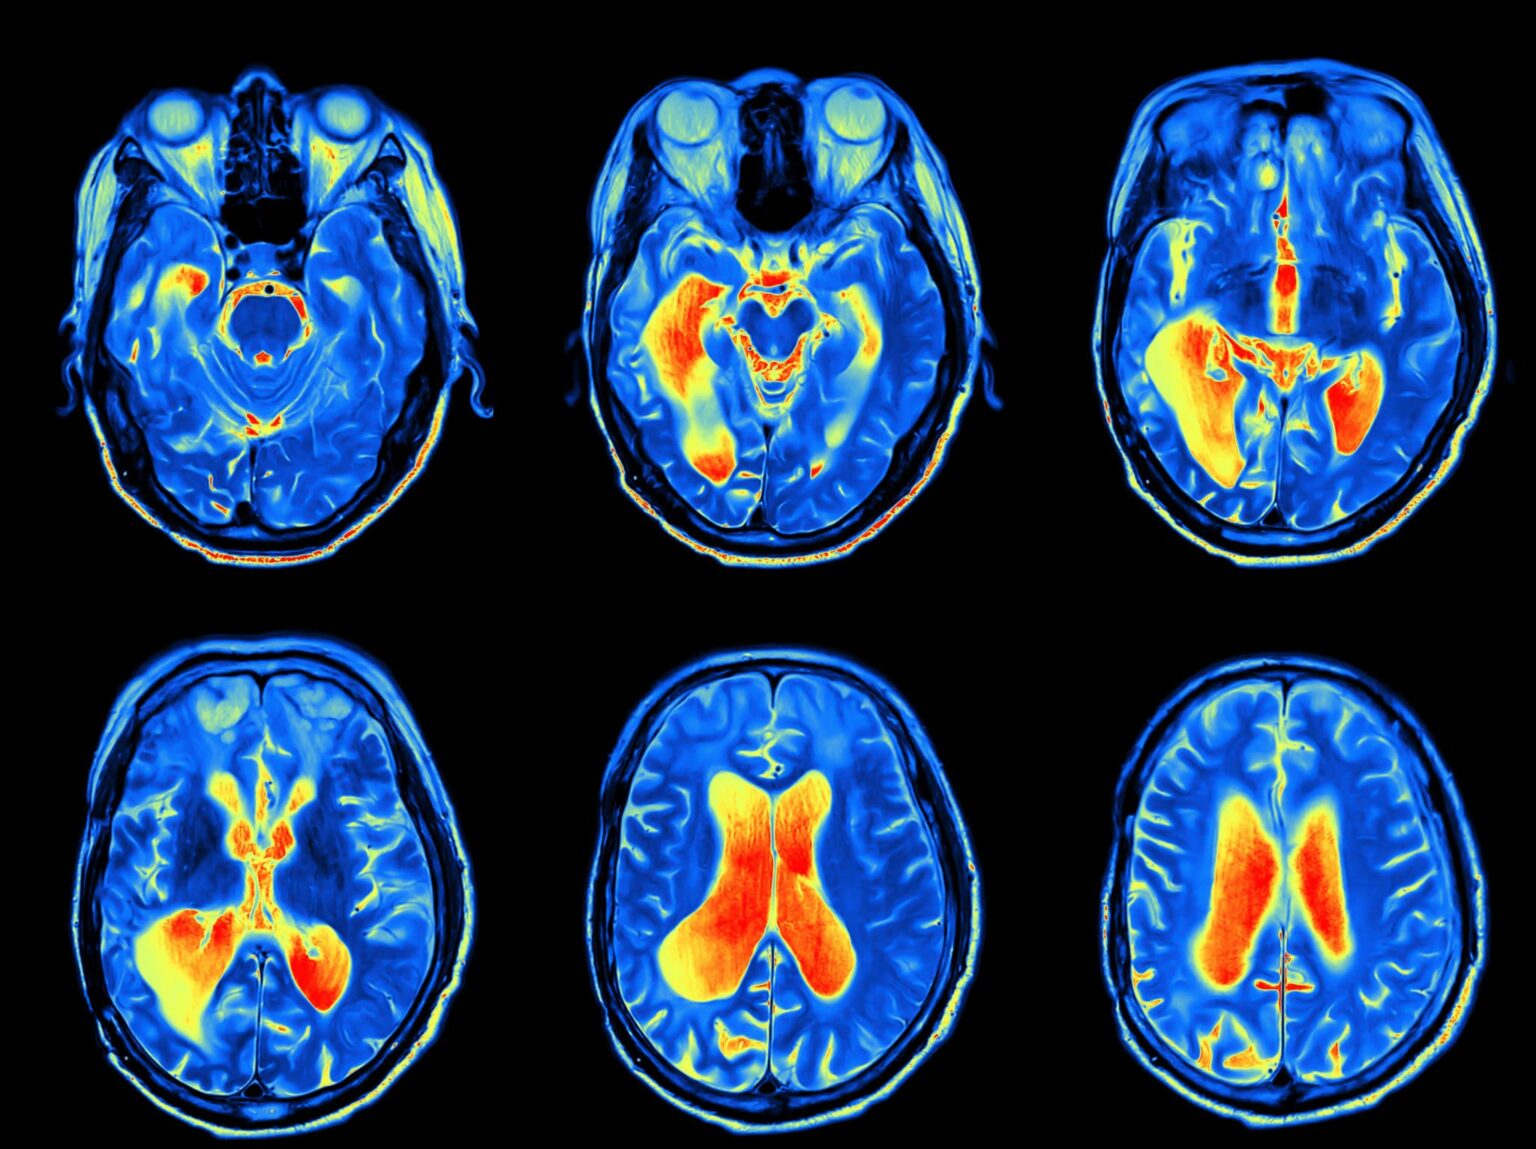

- CT scan

- MRI

- Positron emission tomography (PET) scan